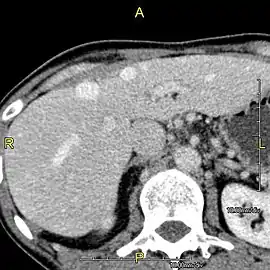

After resection of left lobe liver tumor

Liver transplantation is the only option for those with irreversible liver failure. Most transplants are done for chronic liver diseases leading to cirrhosis, such as chronic hepatitis C, alcoholism, and autoimmune hepatitis. Less commonly, liver transplantation is done for fulminant hepatic failure, in which liver failure occurs rapidly over a period of days or weeks.